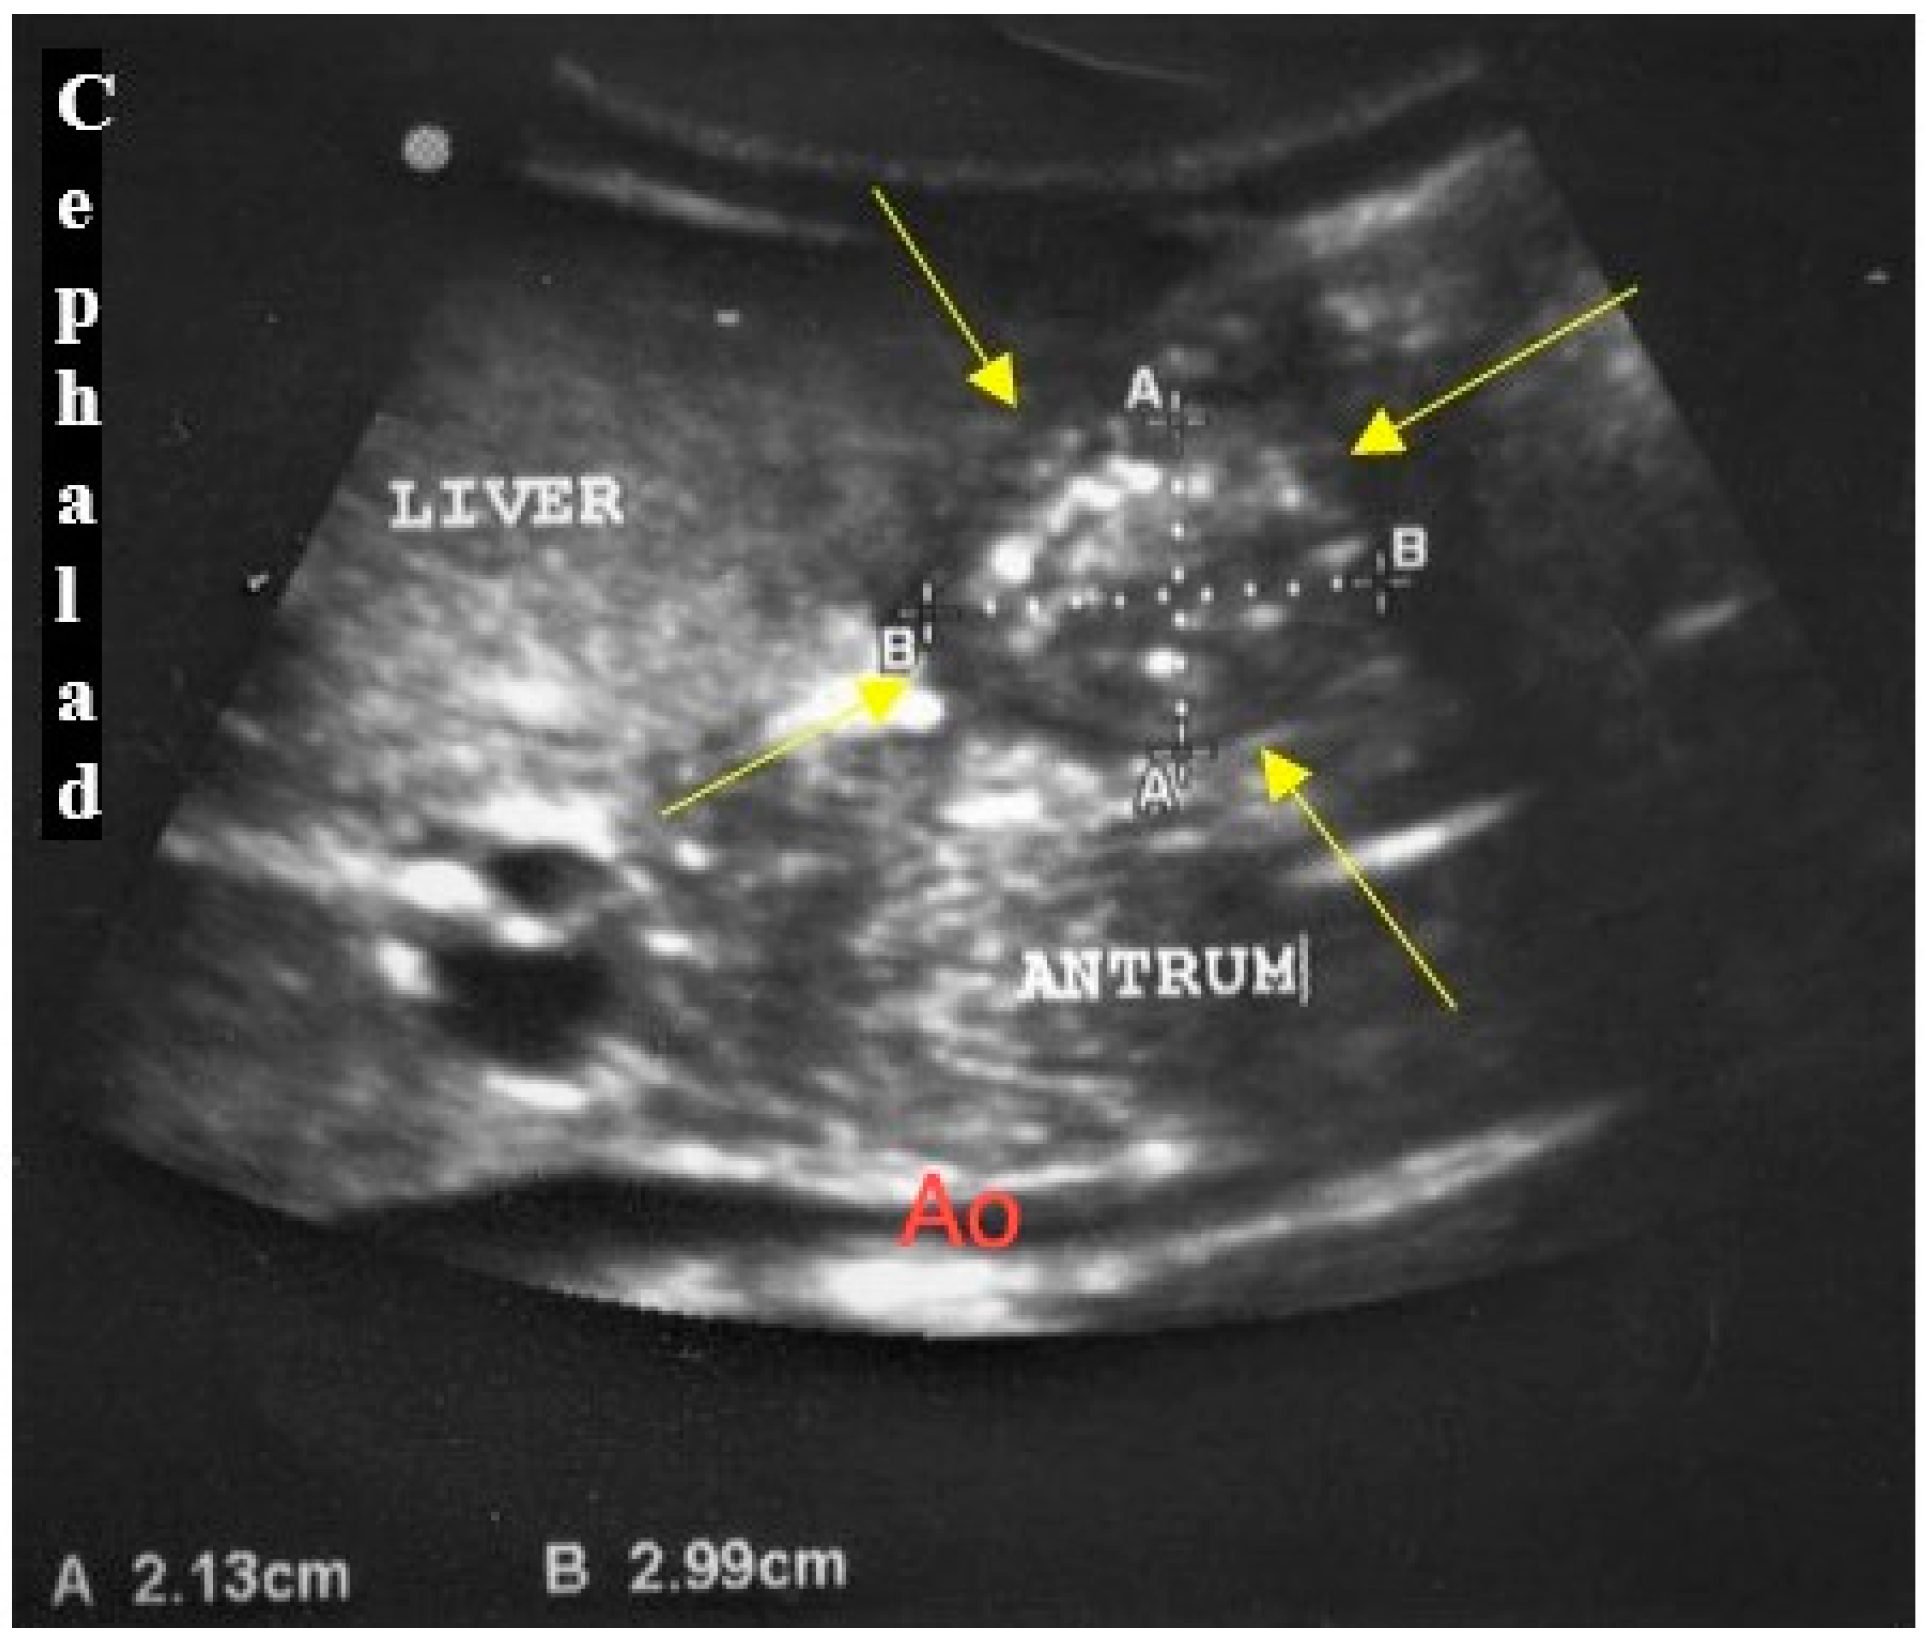

2. Materials and Methods

3. Results